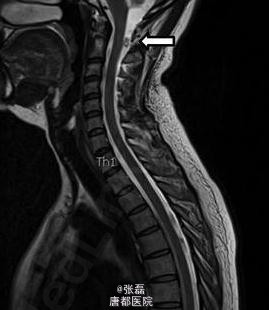

患者女性,46 岁,因头疼加重 2 周住院。住院时表现为颈部僵硬,伴有眩晕。头颅 MRI 未见明显异常。脑脊液结果示:中性粒细胞 133 个 /μl,嗜酸性粒细胞 38%。血清囊虫抗体滴度 106(正常≤0)。 脊髓 MRI 示:颈部单发囊性占位,腰部蛛网膜下腔多发囊性占位。故诊断为脊髓囊虫病,给予阿苯达唑 (2×400 mg/ 天) 驱虫、激素(强的松 60 mg/ 天)抗炎治疗 4 周。治疗期间,患者症状明显缓解,但是在随访 6 个月时,颈部疼痛仍未见缓解,MRI 示颈部囊性占位体积有所增大。